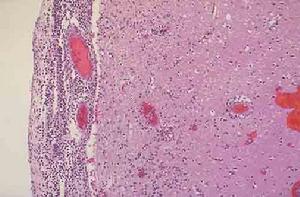

細菌性腦膜炎--病菌社區獲得性細菌性腦膜炎的歷史無疑是反映抗生素出色效果的一個最好例子。在臨床使用特效抗血清以前,各種細菌性腦膜炎患者的預後極差。美國波士頓兒童醫院報告,20世紀20年代,該院78例流感嗜血桿菌性腦膜炎患兒死亡了77例;同樣,未得到治療的肺炎球菌性腦膜炎患者的預後也極差,300例病人全部死亡;20世紀第一個10年內,那些未進行治療的腦膜炎球菌性腦膜炎患者的病死率為75%-80%。套用抗血清治療細菌性腦膜炎